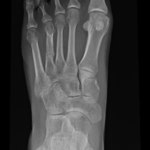

Posttraumatic bone deformities are fractures that heal in a displaced, angulated, rotated, or shortened position.

Fractures can heal in an incorrect position with shortening, angulation or rotation. This is called a malunion.